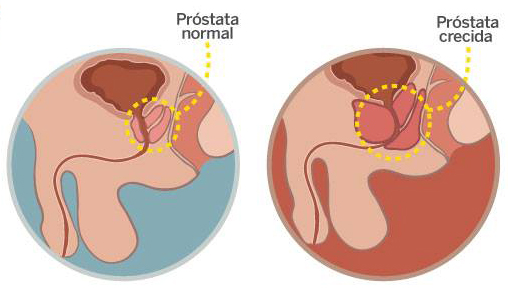

Uno de cada dos hombres mayores de 50, sufre hiperplaxia benigna de próstata

La mitad de los hombres mayores de 50 años sufre hiperplasia benigna de próstata (HBP), una dolencia que genera serias dificultades para orinar y que puede incluso provocar disfunción eréctil. Según datos de la Asociación Española de Urología (AEU), unos 4 millones de hombres mayores de 50 años -el 50 por ciento- y más de 770.000 mayores de 80 años … Continuar leyendo Uno de cada dos hombres mayores de 50, sufre hiperplaxia benigna de próstata